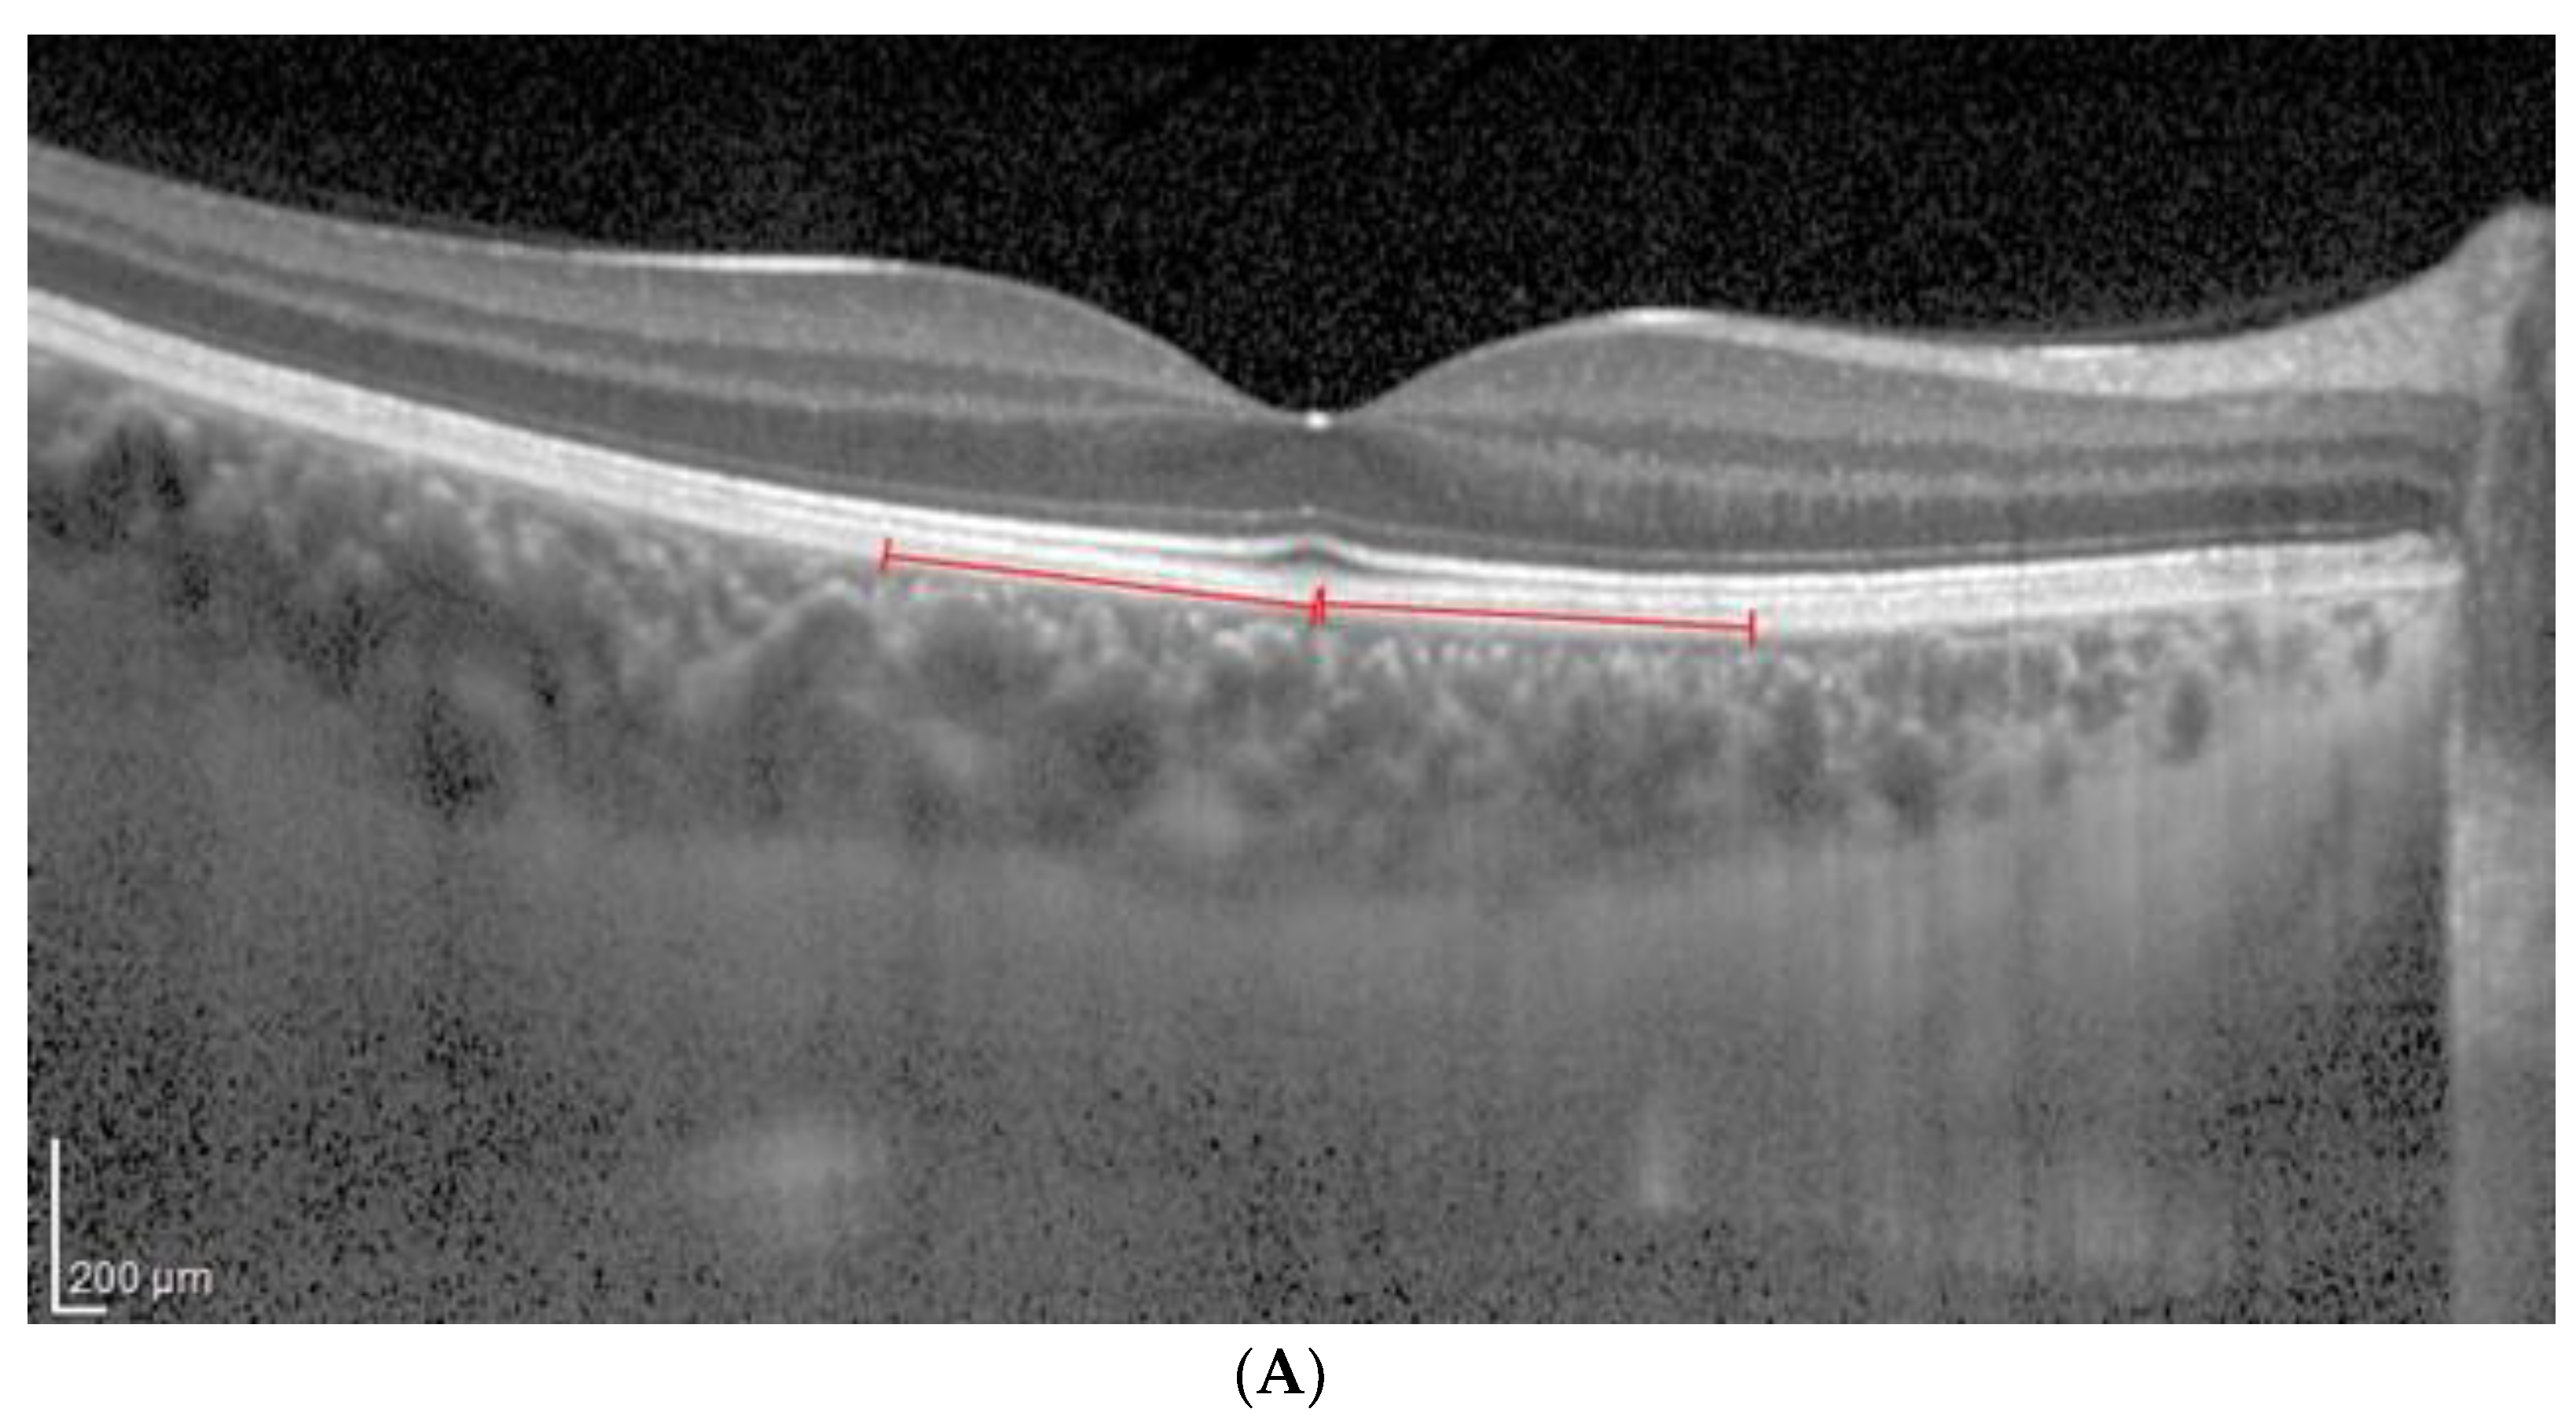

2.3. OCT Analysis

- A classic manual tracking method, manually drawing the lines to limit the choroidal area for each high and low brightness level [2].

- An alternative method, with a fixed area selection independent of the brightness level.